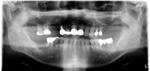

レントゲン写真

治療前 レントゲン写真

治療後 レントゲン写真

60才代 男性

総額:530万円(税別)

治療期間:2年

リスク副作用:経年的変化による補綴物の消耗。ブラッシング不足ですとインプラント周囲炎になります。